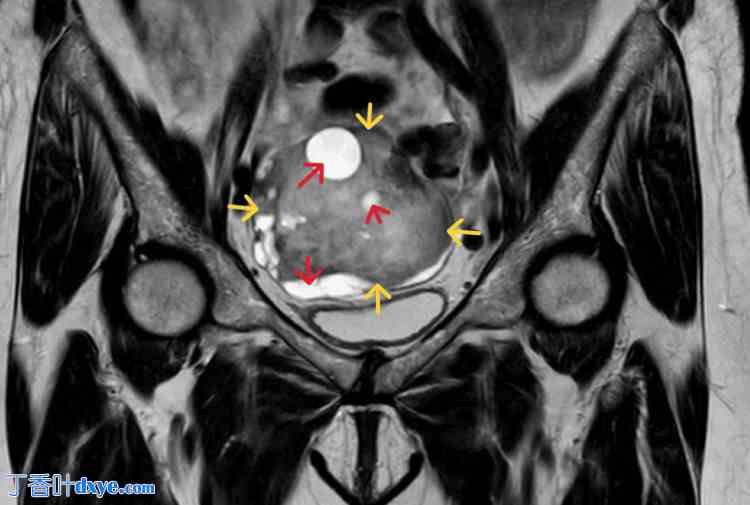

磁共振成像 (MRI) 显示 T1 序列上病灶呈低信号。T2 序列上病灶呈低信号,并伴有囊性变性征象。病灶呈均匀强化,周围区域未见异常淋巴结(图 3)。

图 3. 卵巢卵泡膜细胞瘤的 MRI 图像。

病灶在 T1 和 T2 序列上均呈低信号(黄色箭头),并伴有囊性变性征象(红色箭头)。